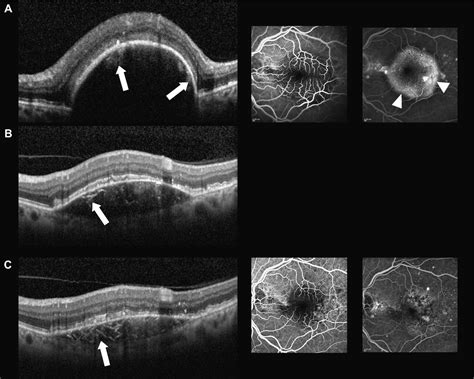

For individuals facing the risk or diagnosis of vision-threatening conditions, Optical Coherence Tomography (OCT) has revolutionized the way eye care professionals monitor retinal health. When it comes to Optical Coherence Tomography Macular Degeneration, this non-invasive imaging technology serves as the gold standard for both early detection and long-term management. By providing high-resolution, cross-sectional views of the retina, OCT allows ophthalmologists to visualize the microscopic layers of the macula, identifying subtle changes long before they manifest as significant vision loss.

OCT works similarly to an ultrasound, but instead of using sound waves, it utilizes light waves to capture images. Because light travels much faster than sound, OCT can achieve a level of detail that is nearly equivalent to an optical biopsy. When a patient undergoes an OCT scan for suspected Optical Coherence Tomography Macular Degeneration, the device measures the reflection of light from the various layers of the retina.

• Identify the presence and size of drusen.

• Detect subretinal fluid or intraretinal edema caused by leaking vessels.

• Measure retinal thickness to track atrophy over time.

One of the most critical aspects of Optical Coherence Tomography Macular Degeneration management is the ability to detect disease activity before the patient experiences symptomatic vision changes. In the “dry” stage, OCT can highlight the presence of intermediate drusen, prompting more frequent monitoring. In the “wet” stage, the immediate detection of fluid accumulation allows for timely intervention, which is vital for preserving remaining vision.

The field of retinal imaging continues to evolve rapidly. Newer versions of the technology, such as OCT Angiography (OCTA), allow doctors to visualize the blood flow within the retina without the need for intravenous dye. This is a game-changer for patients with Optical Coherence Tomography Macular Degeneration, as it provides a non-invasive way to identify neovascularization—the hallmark of wet AMD—with unprecedented clarity.